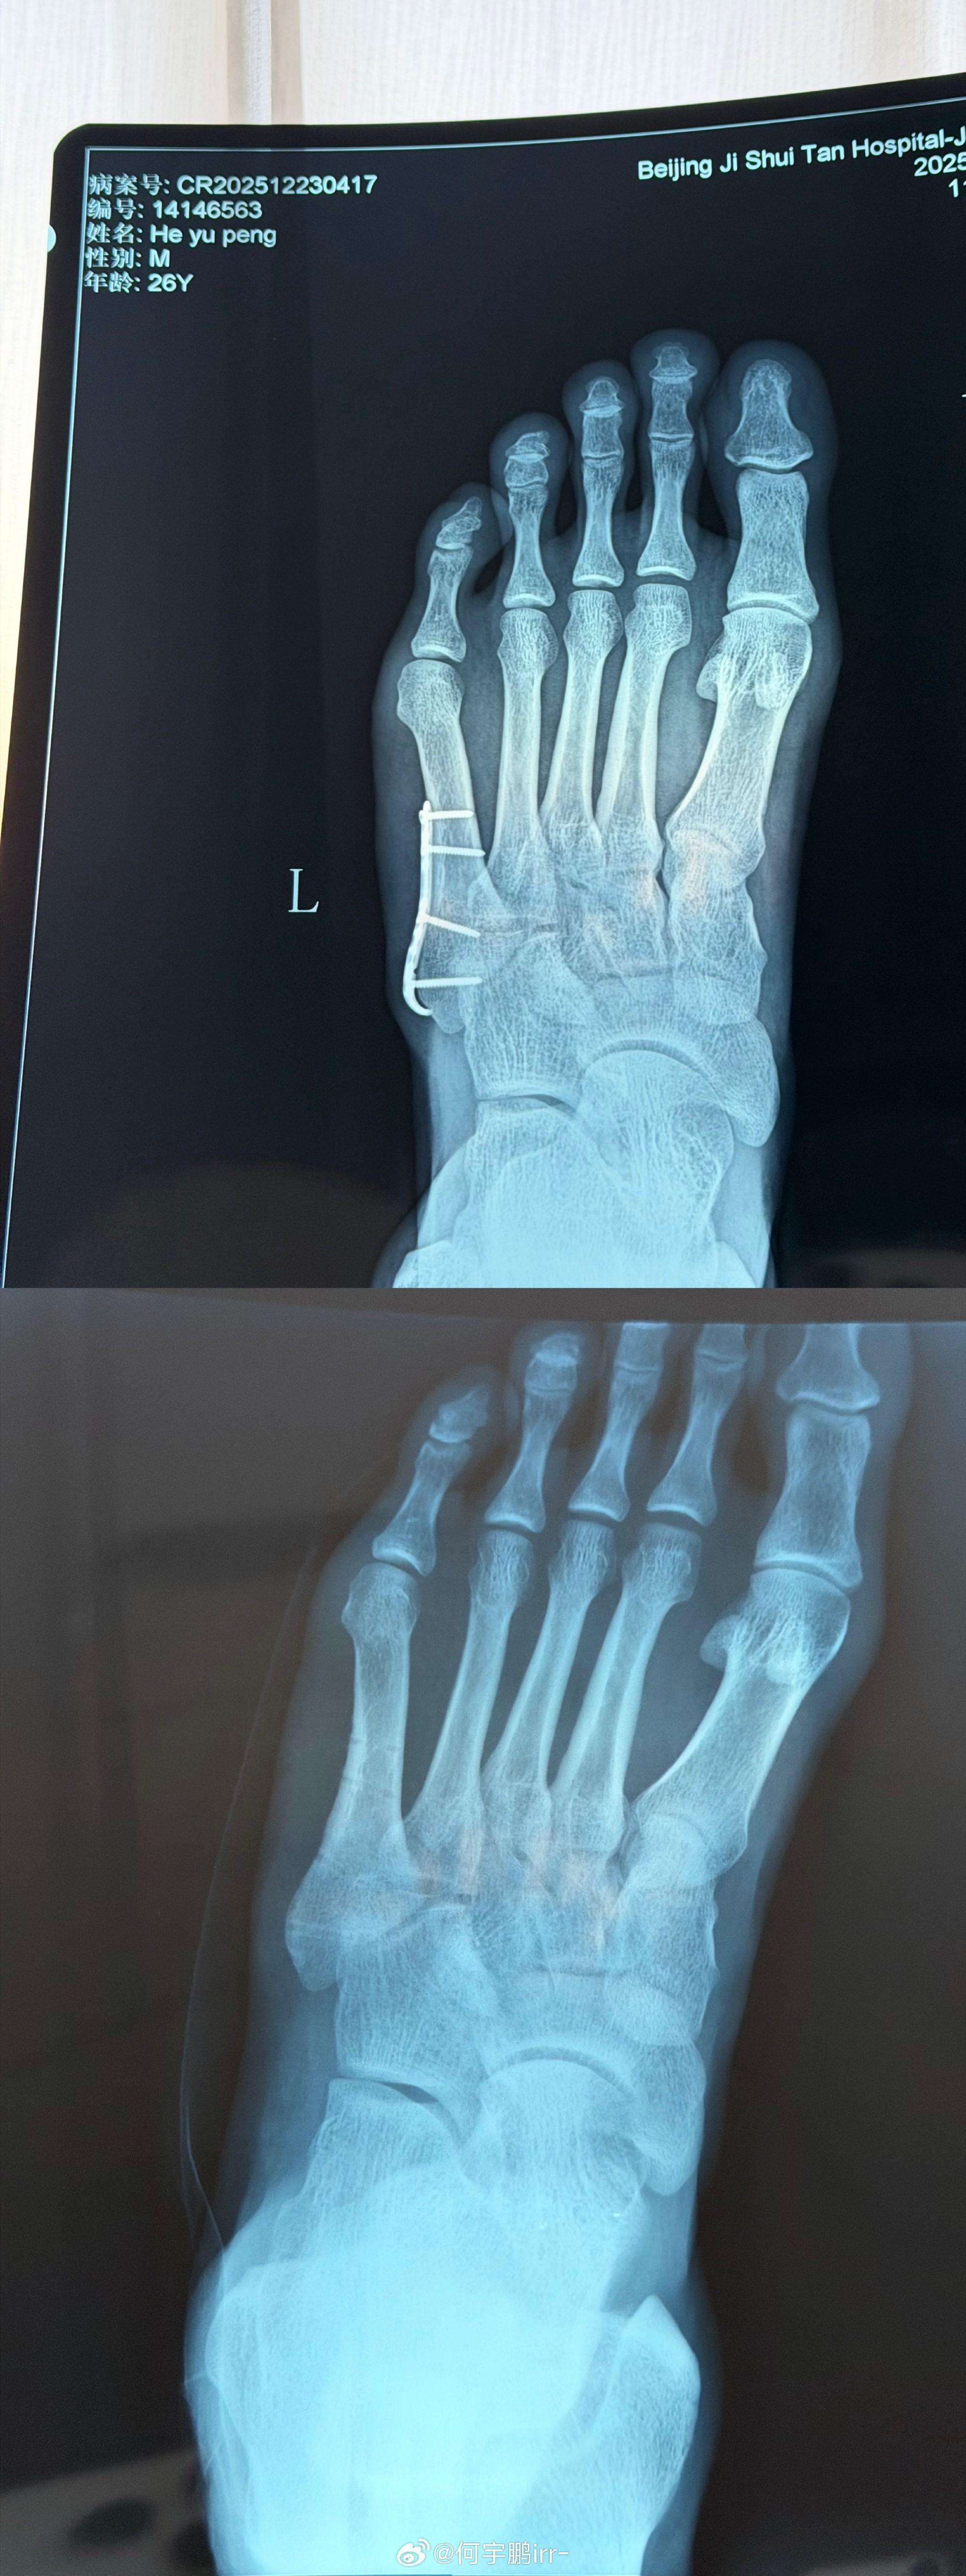

北京時間12月25日,北京國安球員何宇鵬在社交媒體上分享了自己摘除左腳鋼板的照片。

何宇鵬寫道:“終于要和身體里這個‘鐵哥們’說再見了

雖說為了你足球鞋都大了半碼哈哈哈!但也非常感謝8個月的保駕護航,現(xiàn)在,是時候說再見了! 從一開始不敢置信可以帶著鋼板踢球,到二次手術(shù)圓滿結(jié)束,都不得不提我的大功臣,感謝積水潭孫旭主任用超高的醫(yī)術(shù)精密地修補了我的身體! 也感謝葆石頭康復與 的鼎力支持!愿每一次傷愈都能變得更堅韌!”